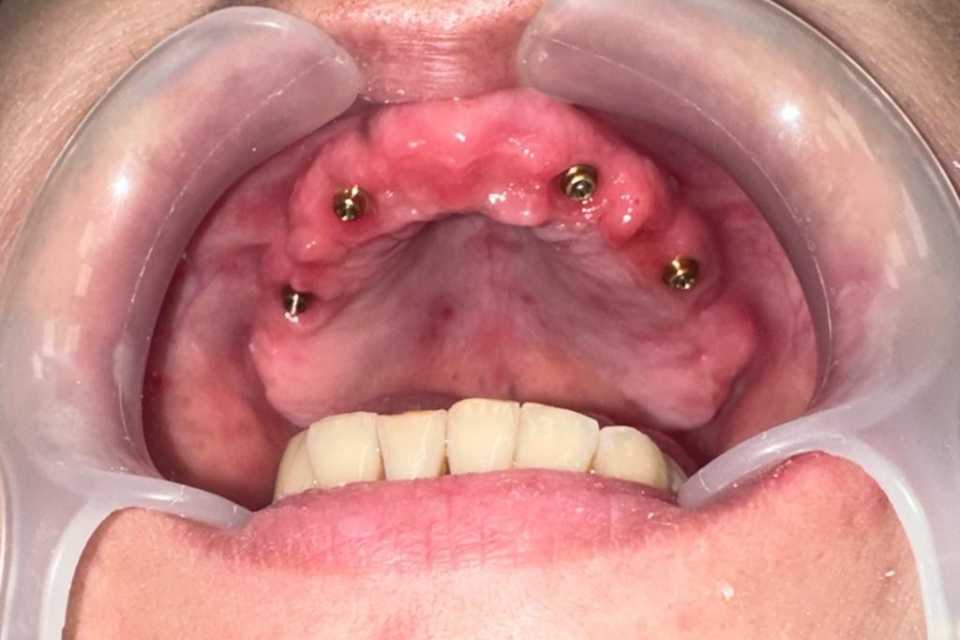

În urma examenului de specialitate, s-a constatat prezența unei punți totale la nivelul maxilarului și a două lucrări vechi la nivelul mandibulei, în zonele laterale premolar-molar. Dintii stâlpi prezentau multiple pungi parodontale, leziuni apicale și mobilitate accentuată.

Împreună cu pacienta, am optat pentru un tratament complex, realizat într-o singură ședință. S-au efectuat extracțiile dinților parodontotici, chiuretajul pungilor parodontale și inserarea a 4 implanturi Mega-Gen AnyRidge la nivelul maxilarului. Cu ajutorul capelor multiunit, s-a reușit protezarea imediată, prin aplicarea unei lucrări provizorii din acrilat, la doar 24 de ore de la intervenție. După 2 luni, tratamentul a fost finalizat prin realizarea unei lucrări definitive, înșurubabile, din ceramică pe suport de zirconiu, cu 12 elemente.